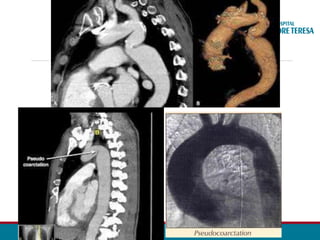

ANGIOTOMOGRAFIA DA AORTA TOTAL – 28/05:

• Presença de volumosa dilatação aneurismática do segmento tubular

ascendente aórtico, com o diâmetro de até 74 mm, sem trombo.

• Nota-se a redução moderada do diâmetro luminal aórtico do arco, sendo

mais intenso na região do istmo (diâmetro mínimo luminal efetivo no istmo é

de aproximadamente 6,5 mm), havendo dilatação fusiforme pós-

estenótica no terço proximal descendente aórtico com até 36 mm.

• O segmento mais distal descendente da aorta apresenta o diâmetro normal.

• São evidenciadas diversas artérias dilatadas moderadamente

intercostais da metade superior, bilaterais, notando-se ainda leve /

moderada dilatação bilateral das artérias torácicas internas.

•Artérias ilíacas comuns, internas e externas estão patentes.

ANGIO TOMOGRAFIA

• Segmento estenosado

• Circulação colateral

• Planejamento cirúrgico

•Acompanhamento pós - OP

Diagnóstico Diferencial

• Pseudocoarctação

• Alongamento e Kinking do arco aórtico.

• Pode formar “ duas proeminências” no local do arco

aórtico, simulando o Sinal do 3.

• Ausência de obstrução do fluxo sanguíneo.

• Ausência de vasos colaterais.

• > idade